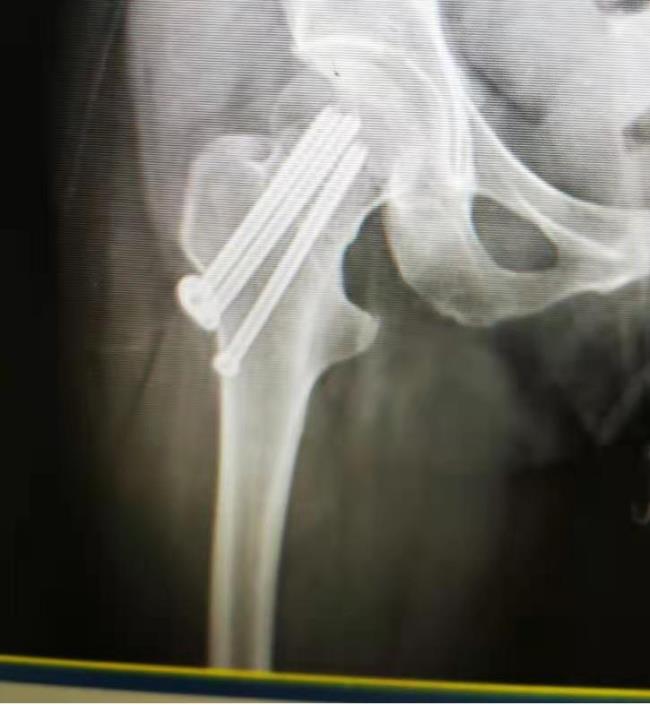

闭合复位经皮穿钉固定技术

闭合复位经皮穿钉固定技术治疗四肢骨折创伤小、疗效好,该技术获广西科学技术进步奖三等奖。